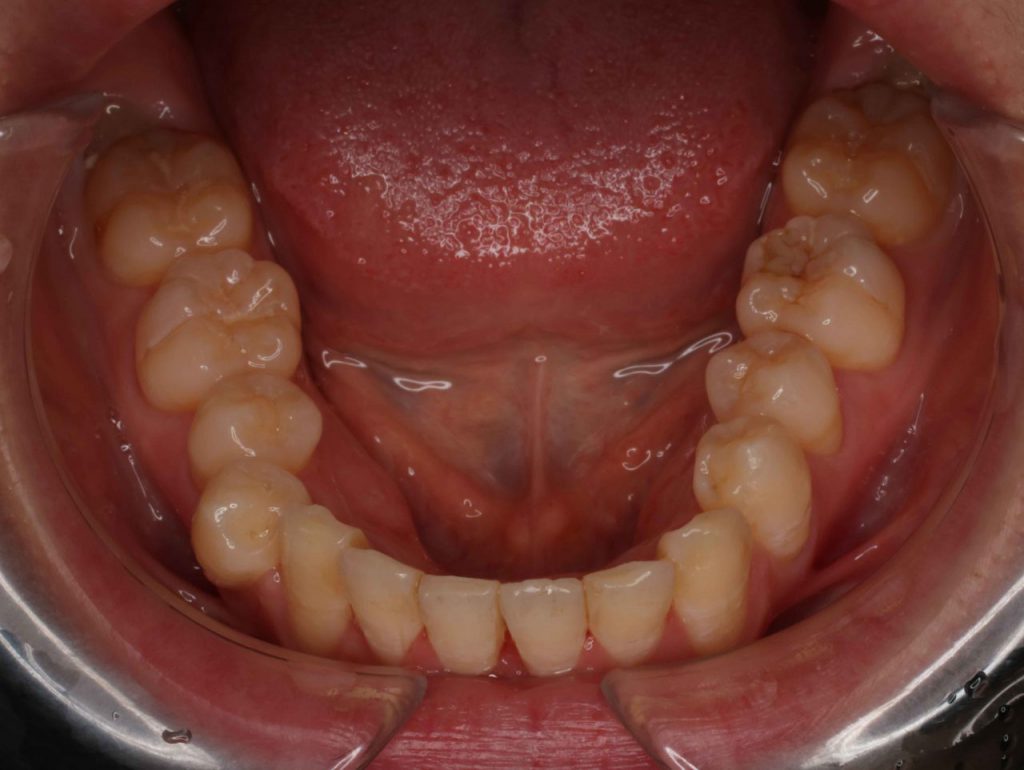

After

After

| 治療内容 | マルチブラケット法(部分矯正) |

| 治療期間 | 8ヶ月 |

| 費用 | 576,400円 |

矯正費用をできるだけ抑えたい治療期間を短くしたいとのご希望で上下前歯のみの部分治療で歯に直接装置を付ける(ダイレクトボンディング ブラケット)方法で行いました、前歯の歯の間を削り(IPR)各々の歯を少し細くして歯を並べるスペースを作りました。2296